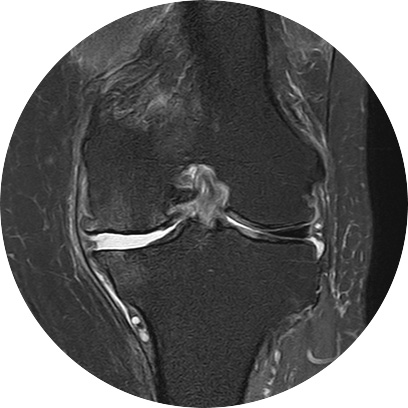

관절 마모 정도가 심하고 통증이 심한 환자분들은 재활치료나 약물만으로는 치료가 어려운 경우가 있습니다.

손상된 무릎 뼈를 제거하고, 그 부위에 특수 소재의 금속 재질로 구성된 인공관절을 삽입하는 수술을 시행할 수 있습니다.

관절연골이 망가져 쓸 수 없을 때 관절기능 회복을 위해 시행하며, 인공관절의 수명은 20~30년 정도 됩니다.

인공관절수술은 이러한 환자분들을 대상으로 시행하는 수술로

정밀검진 및 검사를 통해 관절 손상정도를 면밀히 파악하고 꼭 필요한 경우에만 수술을 진행합니다.